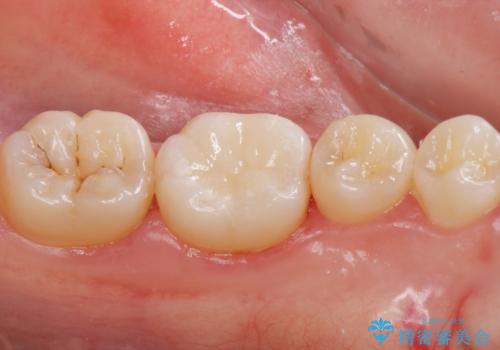

白い歯にしたいとの事だったのでセラミックインレー(e-maxインレー)にて治療しました。

セラミックの詰め物は銀の詰め物に比べて適合がよく、虫歯の再発のリスクが少なくなります。白い詰め物が入り大変満足して頂けました。